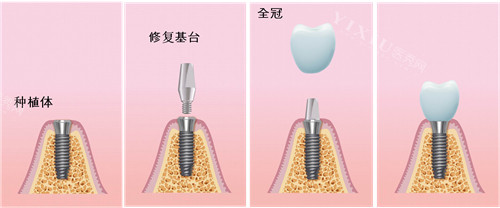

一、台州种植牙价格表:国产 2380 元起,韩系 / 欧美 / 亲水款全覆盖

种植牙是缺牙修复的 “黄金方案”,台州牙科医院根据种植体品牌、技术难度、患者骨质条件,提供多档选择:

国产种植牙(创英 / 百康特):2380 元起 / 颗(基础款,适合单颗缺失预算有限人群)

韩国登腾种植牙:2980 元起 / 颗(性价比之选,骨结合快,临床应用超 20 年)

韩国奥齿泰种植牙:3500 元起 / 颗(纳米涂层技术,适合骨质一般患者)

美国皓圣种植牙:4800 元起 / 颗(独特螺纹设计)

德国 ICX 种植牙:6800 元起 / 颗(初期稳定性强,适合咀嚼力要求高者)

瑞士 ITI 种植牙:9800 元起 / 颗(种植界 “金标准”,亲水款骨结合速度提升 30%)

瑞典诺贝尔种植牙:10800 元起 / 颗(长期质保,适合全口 / 半口缺失)

半口半固定种植牙(4 颗植体):2.5 万元起(覆盖义齿,适合半口缺牙)

All-on-4 半口即刻负重:5 万元起(当天种牙当天用,含智能化导板)

全口 All-on-6 种植牙:12 万元起(上下颌各 6 颗植体,长期稳定)